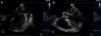

Transthoracic echocardiography (TTE) showed multiple aortic valve vegetations (some prolapsing into the left ventricular outflow tract), mild aortic regurgitation and a large saccular bulge originating from the anterior mitral valve leaflet and protruding into the left atrium with severe mitral regurgitation (Figure 1); left ventricular systolic function was normal. With transesophageal echocardiography (TEE) it became clear that the saccular bulging on the mitral valve was an anterior mitral valve leaflet aneurysm with two rupture sites (Figure 2). Color flow Doppler showed two regurgitant jets: one through the coaptation margin of the mitral valve leaflets and the other across the perforated aneurysm (Figure 3). There was no evidence of either aortic ring abscess formation or extension along the mitral-aortic intervalvular fibrosa.

Transthoracic echocardiogram (parasternal long-axis view). (A) Saccular bulge on the atrial side of the anterior mitral valve leaflet (small arrow) and a vegetation on the aortic valve prolapsing into the left ventricular outflow tract, in close contact with the anterior mitral valve leaflet (long arrow); (B) significant mitral regurgitation (color flow Doppler).